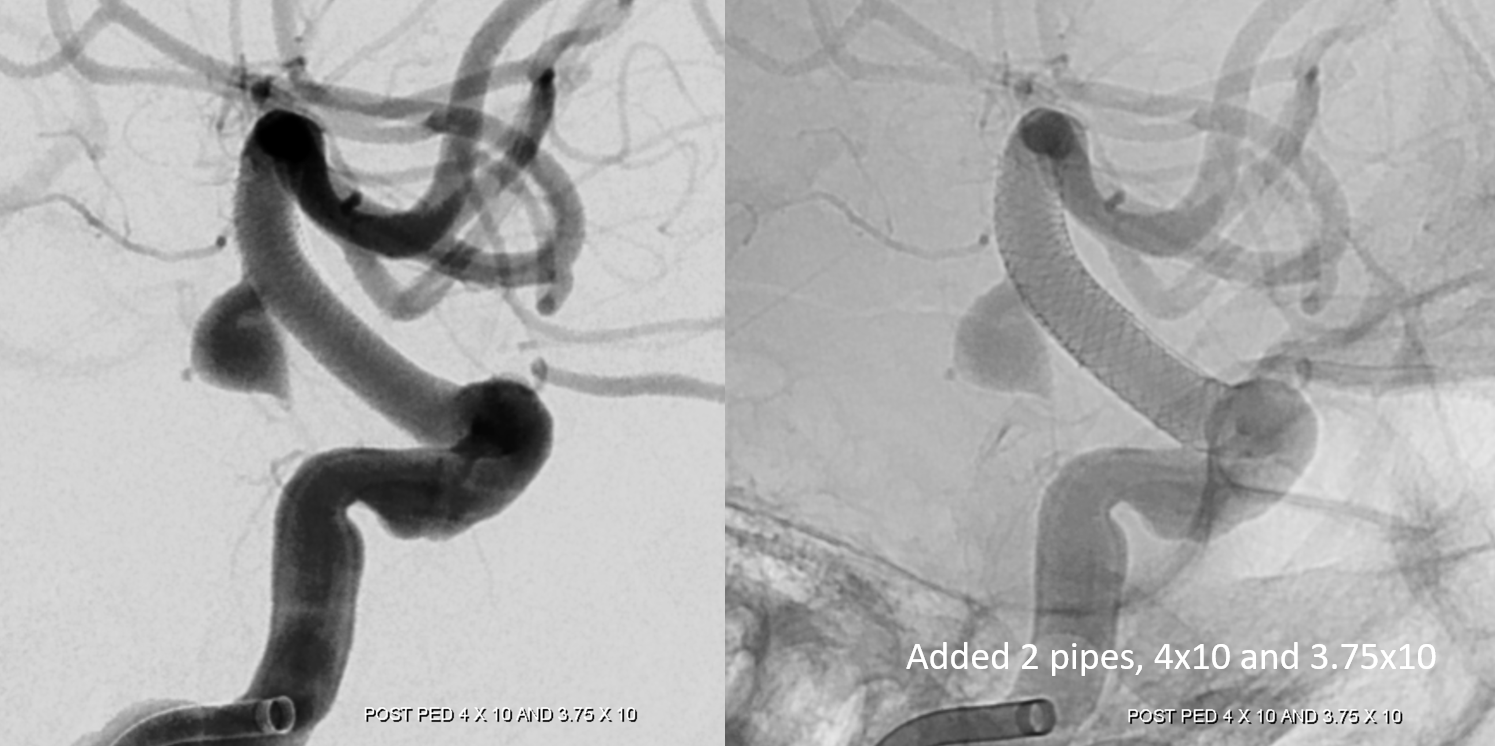

Two years later — two more pipes are added. Can one argue this is a mistake — if two did not do it, will four? Its a valid point, as you can guess

One year after, still here… What we dont understand is why. What we do know is that one Pipe would have surely not been enough. It is also possible that having all these Pipes stopped the aneurysm from growing much more… Never know, but we have sure seen what happens when these are underterated